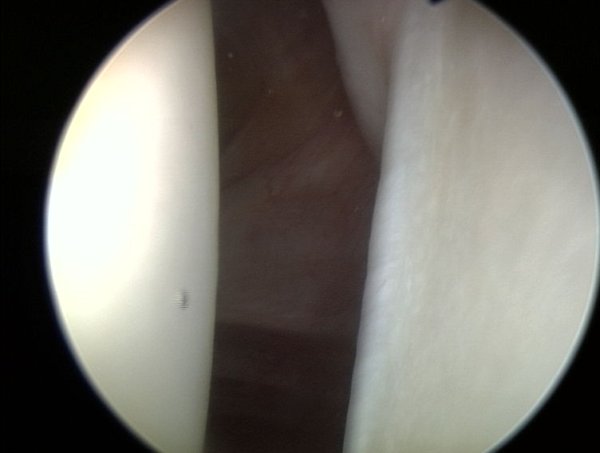

" Naciąganie opony " czyli umieszczenie obrąbka na panewce w anatomicznej pozycji. Przyczepianie obrąbka odbywa się przy pomocy tzw. kotwiczki, ktorą może być z metalu lub biowchłanialna.

Tutaj widoczny jest ten sam region, po artroskopowej rekonstrukcji obrąbka.